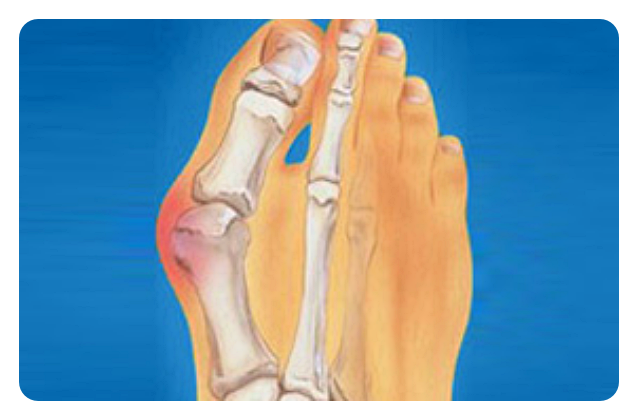

무지외반증은 엄지발가락이 두 번째 발가락 쪽으로 많이 휘고, 엄지발가락과 관절을 이루는 중족골이 안쪽으로 휘어진 형태입니다. 발생 원인은 평발이나 넓적한 발, 과도하게 유연한 발 등으로 생기기도 하며, 후천적으로 높은 굽의 신발이나 하이힐을 자주 사용하는 경우에도 생길 수 있습니다. 또한 유전적으로 발생하거나, 관절염으로 인해 합병증으로 발생하는 경우도 있습니다. 가장 흔히 나타나는 증상은 관절 안쪽의 통증입니다.